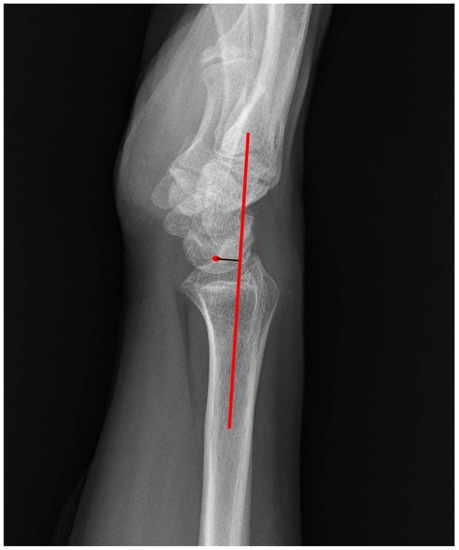

- Kuhnel, S.P.; Bigham, A.T.; McMurtry, R.Y.; Faber, K.J.; King, G.J.; Grewal, R. The Capitate-to-Axis-of-Radius Distance (CARD): A New Radiographic Measurement for Wrist and Carpal Alignment in the Sagittal Plane. J. Hand Surg. 2019, 44, 797.e1–797.e8. [Google Scholar] [CrossRef] [PubMed]

| Lunate-to-Axis-of-Radius distance | 4.3 ± 2.0 mm | 3.5 ± 2.3 mm | 0.028 * |